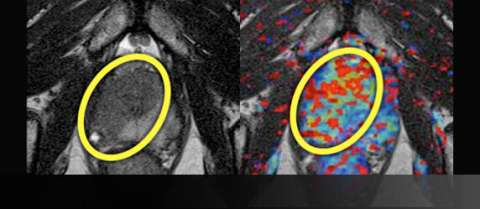

Imaging

LEFT: T2-weighted image prior to treatment shows large, low-signal mass (yellow oval) on the right crossing midline anteriorly

RIGHT: Color perfusion map shows correspondingly increased perfusion (yellow-green pixels) with washout (red pixels)